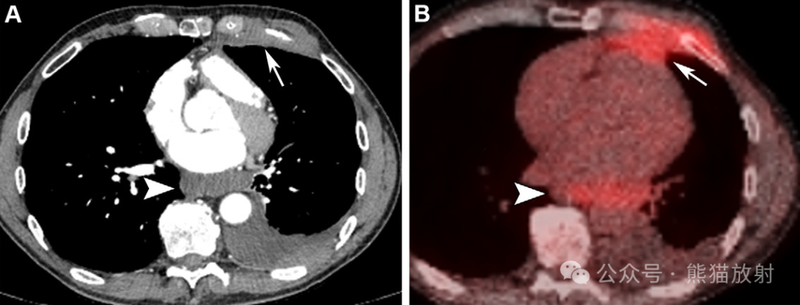

43岁男性,胸膜间皮瘤。轴位增强CT图像(A)及相应轴位18F-FDG PET/CT 图像(B)显示心前区胸膜不规则增厚(箭) 累及胸壁,心后区软组织密度肿块(箭头)。PET/CT图像证明这两个区域病变的摄取增加 (B)。请注意18F-FDG PET/CT 有助于识别隐匿性疾病和淋巴结肿大。

68岁女性,心包间皮瘤。(A) 增强胸部 CT 图像显示心包结节样增厚(箭)和大量心包积液(箭头)。(B,C) 矢状位T2WI (B) 和轴位对比增强T1WI (C) MR 图像显示有强化的T2等信号心包肿块(箭)和心包积液(箭头)。(D) 冠状18F-FDG PET/CT 图像显示明显高代谢的心包肿块 (箭头)。